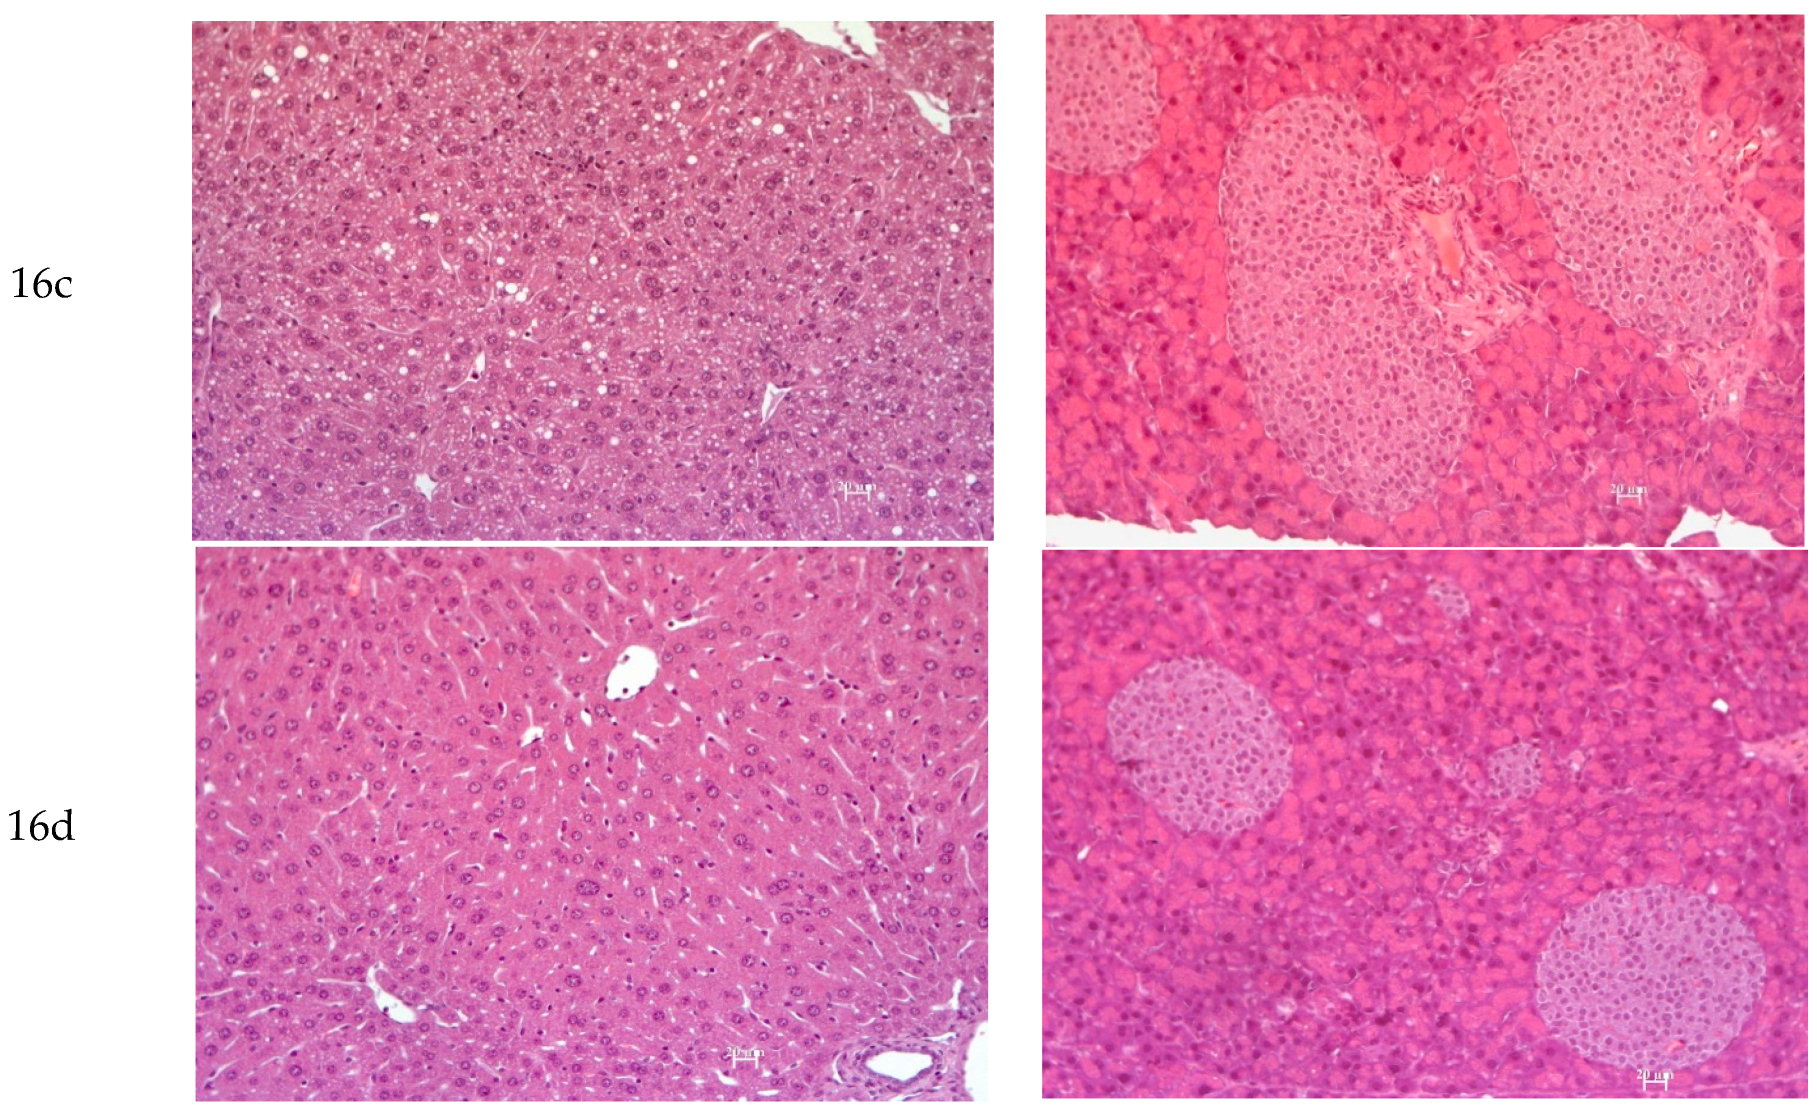

3.2.7. Histology